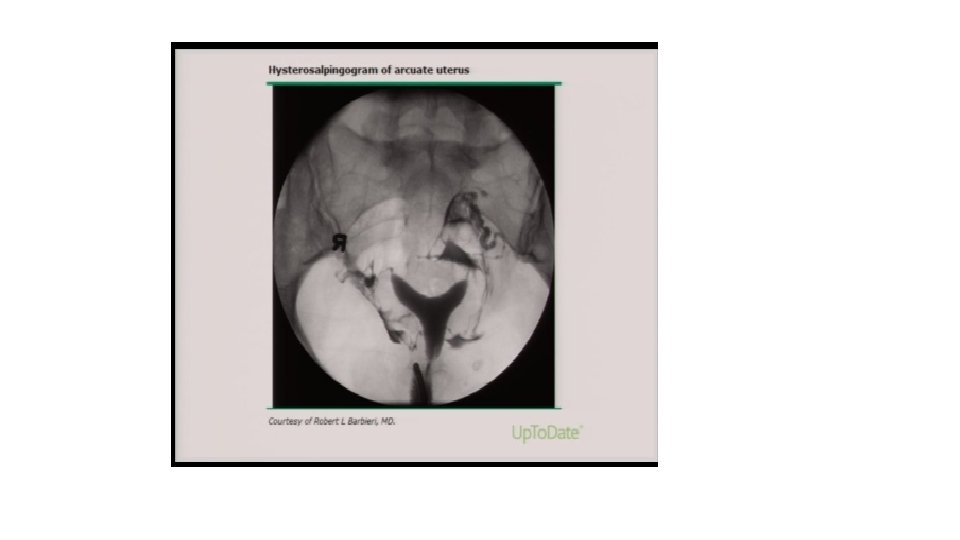

Histerosalpingografi (HSG) • En iyi başlangıç testidir • Uterin kavitenin boyutunu ve şeklini duyarlı bir şekilde tanımlar • Mensin bitiminden hemen sonra 2– 5. gün içinde yapılmalıdır (HSG’de distal tubal obstrüksiyon gösterildiğinde doksisiklin 5 gün boyunca günde iki kez 100 mg endikedir) • Suda ve ya yağda çözünen kontrast madde kullanılarak yapılır • Normal uterin kavite simetriktir, fundusa yakın kornual orifisler düzeyinde genişleyen kabaca üçgen şeklindedir ve göreceli olarak düzgün sınırlıdır • Gelişimsel anormallikleri gösterebilir (unikornis, septa, bikornis) • Edinsel patolojileride gösterebilir (polip, submokaz myom, sineşi)